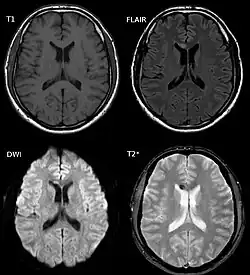

L'imagerie par rayonnement X (Tomodensitométrie, dit scanner X) peut détecter certaines des petites hémorragies survenant simultanément à une LAD[3], mais la plupart seront invisibles et les cas de LAD non hémorragiques ne seront pas détectés. Finalement, cette technique se révèle peu sensible (de l'ordre de 25 % de cas détectés pour un échantillon riche en LAD graves)[13].

L'Imagerie par résonance magnétique (IRM) se révèle plus efficace[3],[13].